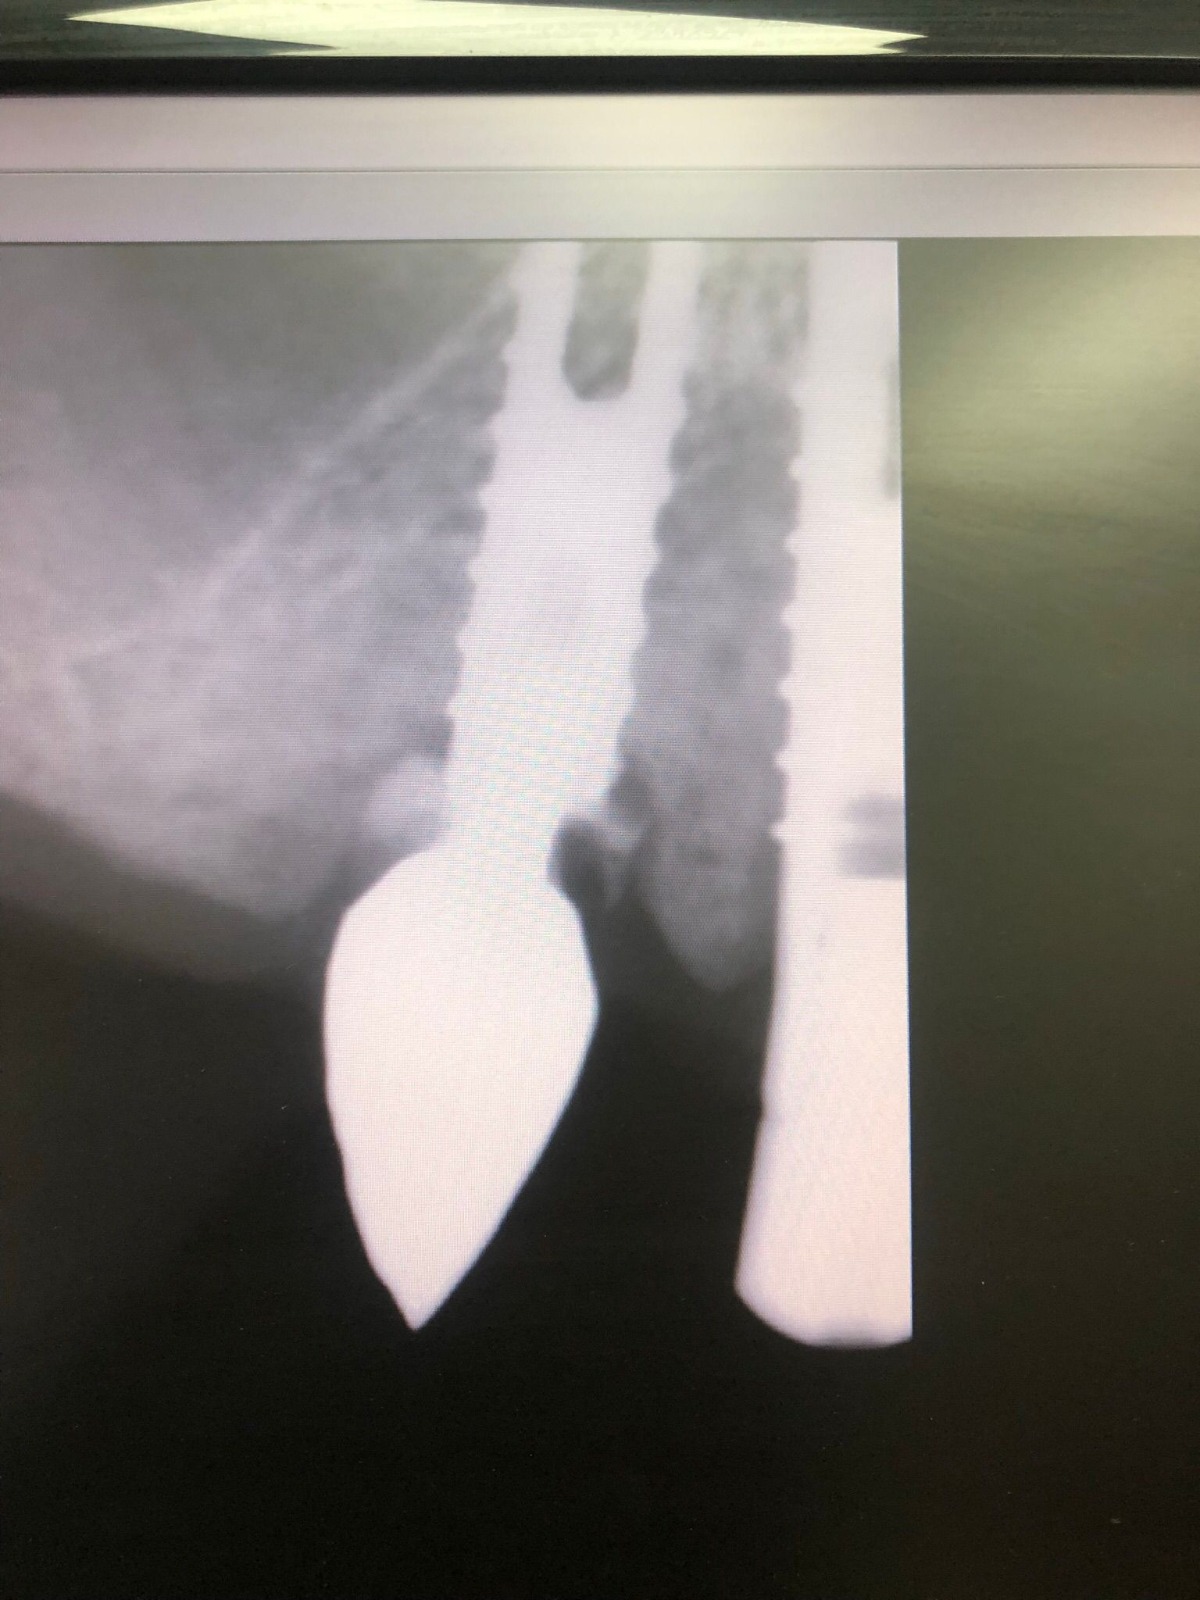

Actualmente vuelve el paciente de nuevo con la misma prótesis. Había roto dos de los tres pilares en concreto los más distales. El primero de los dos había roto la rosca del aditamento dentro del implante como ocurre habitualmente. Pero el ultimo pilar había roto directamente la cabeza del implante tal como se ve en la radiografía y lo que quedaba era un cilindro de titanio macizo perfectamente integrado en el maxilar, sin posibilidad de enroscar nada. Le explicamos al paciente que habría que quitar y poner un implante en el mismo acto. El paciente dijo que no, así que decimos que no se haría cirugía. Buscamos solución alternativa: hacemos un un agujero en el centro del macizo cilíndrico del implante roto y pasamos sucesivamente el set de machos roscantes. Utilizamos una fresa cañón de 1 mm que poco a poco se va introduciendo hasta 8mm con un poco de vagación, que hace que sea un poco mas de 1mm de diámetro. Posteriormente pasamos el conjunto de machos roscantes de métrica 2mm para poder usar un aditamento experimental, que era un palo de rosca de diámetro 2 mm unido a un cuerpo metálico en forma de sombrero napoleónico fabricado en cromo/cobalto, prototipos primitivos de la sistemática ASATIM y que tienen la característica de tener gran resistencia a la fractura. Nos llevó un tiempo largo el tallado de dichos aditamentos, tal como se puede observar en las imágenes, y tras cicatrizar la encía se le hizo una prótesis estándar. Esperemos que no lo rompa más veces.